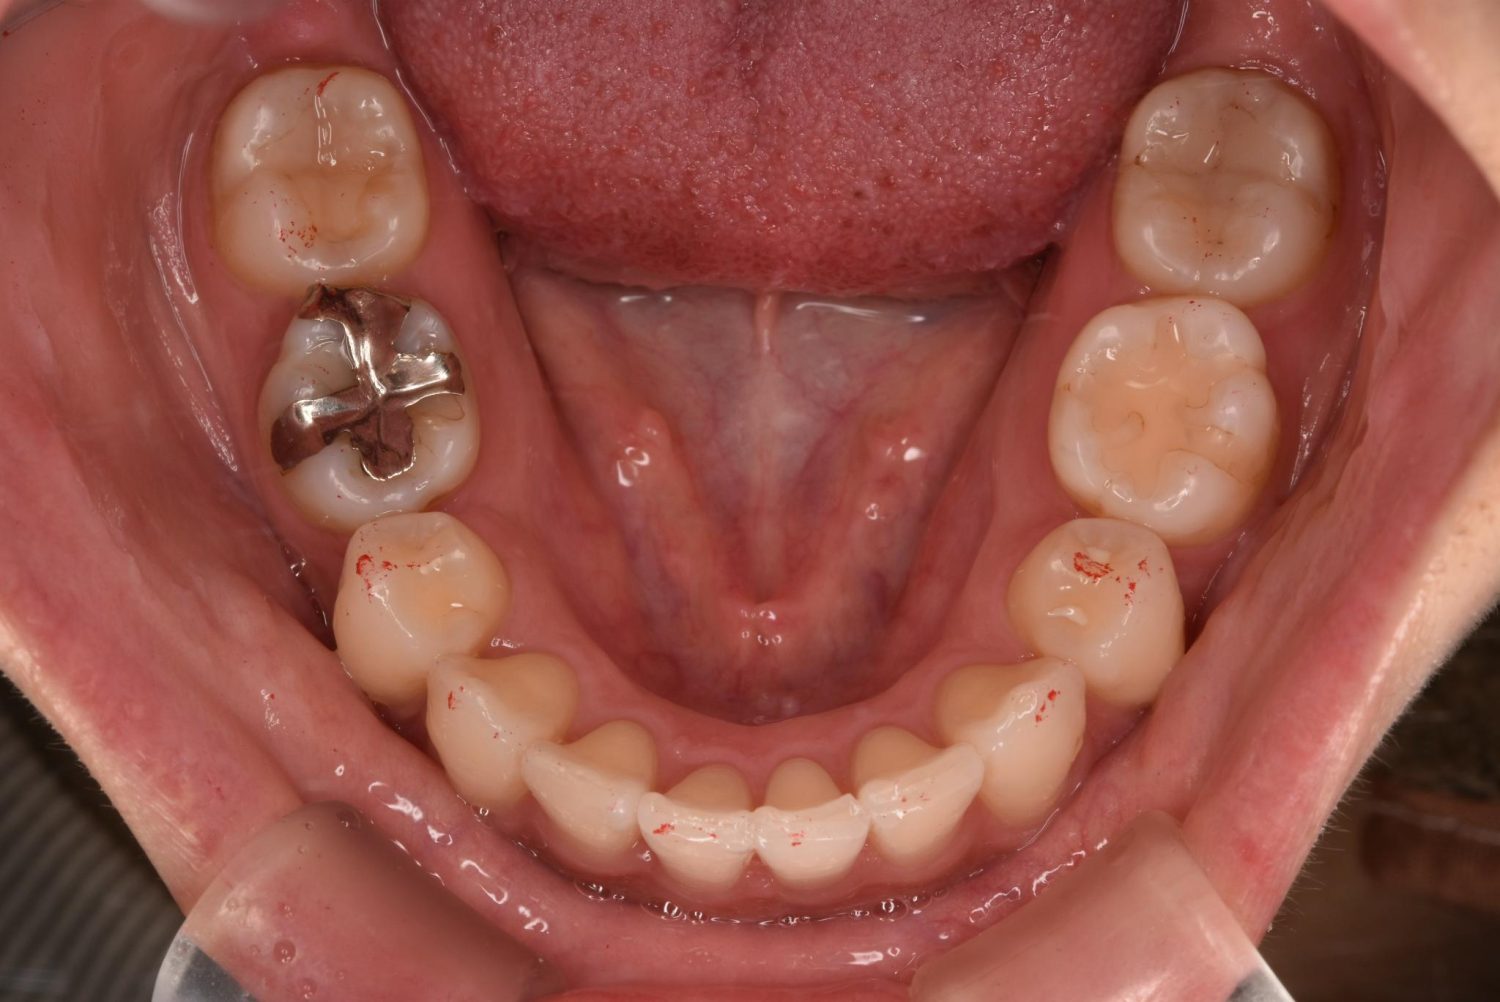

| 主訴 | 20代女性の患者さん。右上の八重歯が突出しており、前歯の見た目にコンプレックスを抱いていた。下顎の左右第2小臼歯(5番)が舌側に大きく傾斜しており、食事の際に、食べかすが詰まりやすく日常的に不快感を覚えていた。噛み合わせの改善と、見た目のバランスを整えたいという希望があり、矯正治療を行うことになった。また、目立ちにくい方法で治療を進めたいという意向から、マウスピース型装置の矯正 “インビザライン”を希望。 |

| 治療内容 | 下顎の左右第2小臼歯(5番)は舌側に大きく傾斜しており、矯正治療における歯の移動効率や全体の歯列バランスを考慮し、便宜抜歯を行った。また、上顎の左右第1小臼歯(4番)についてもスペース確保の目的で抜歯を実施し、全顎的な歯列の配列を円滑に進められるよう計画。矯正装置は、患者さんのなるべく目立ちにくい治療を行いたいという強い希望とライフスタイルに合わせて、マウスピース型矯正装置「インビザライン」(※1)を採用。抜歯が必要となる矯正治療は、診断・治療の難易度が高い方法である。当院ではCTやセファログラムなどの先進的な設備を完備し、多角的な診査診断と豊富な臨床経験をもつ理事長による治療を行うことで、このような難症例にも対応可能。 また、当院は矯正治療だけでなく、むし歯治療やクリーニングなどの一般歯科・予防治療も一貫して管理する包括的な審美治療を行う総合クリニック。治療中にむし歯などの問題が見つかっても、すぐに対応できるため、患者さんの通院の負担をできる限り抑えたスムーズな対応が可能。矯正専門医院ではできない包括的なサポート体制こそが、シャングリラデンタル横浜歯科矯正歯科で矯正治療を受けるメリットである。 矯正治療中は定期検診で経過の確認とクリーニングを行い、必要に応じて治療計画の見直しやマウスピース型装置の追加を行った。患者さんの高い装着遵守率も相まって、歯列は順調に整い、機能的にも審美的にも良好な結果をえることができた。 (※1)未承認医薬品等であるため医薬品副作用被害救済制度の対象とはならない可能性があります。 |